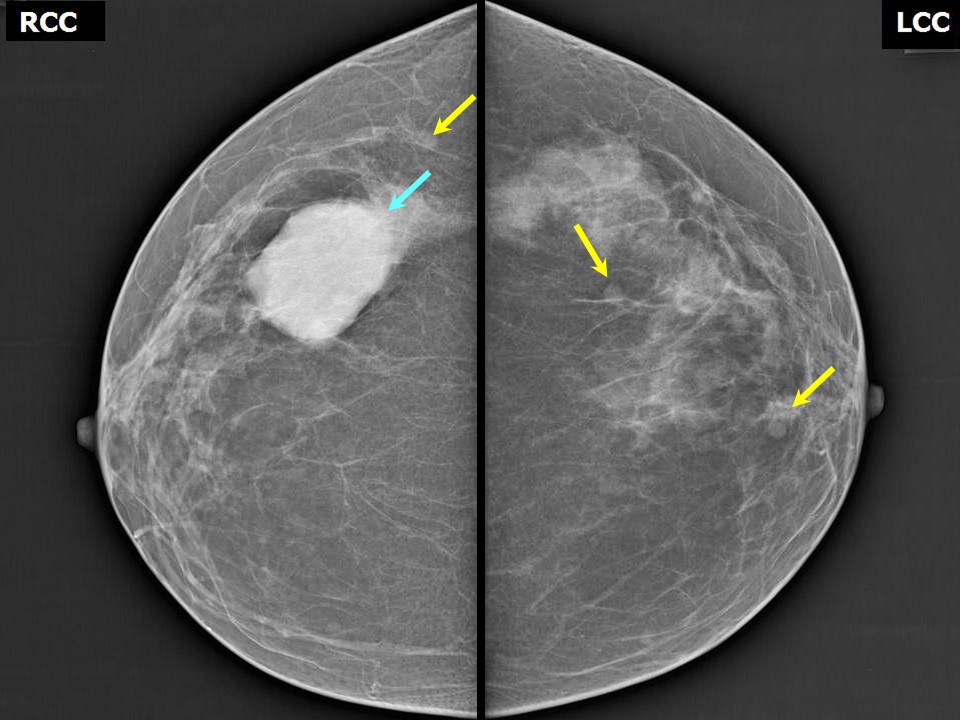

Феномен гипердиагностики в маммографии: примеры и иллюстрации

Раздел: Образы вокруг